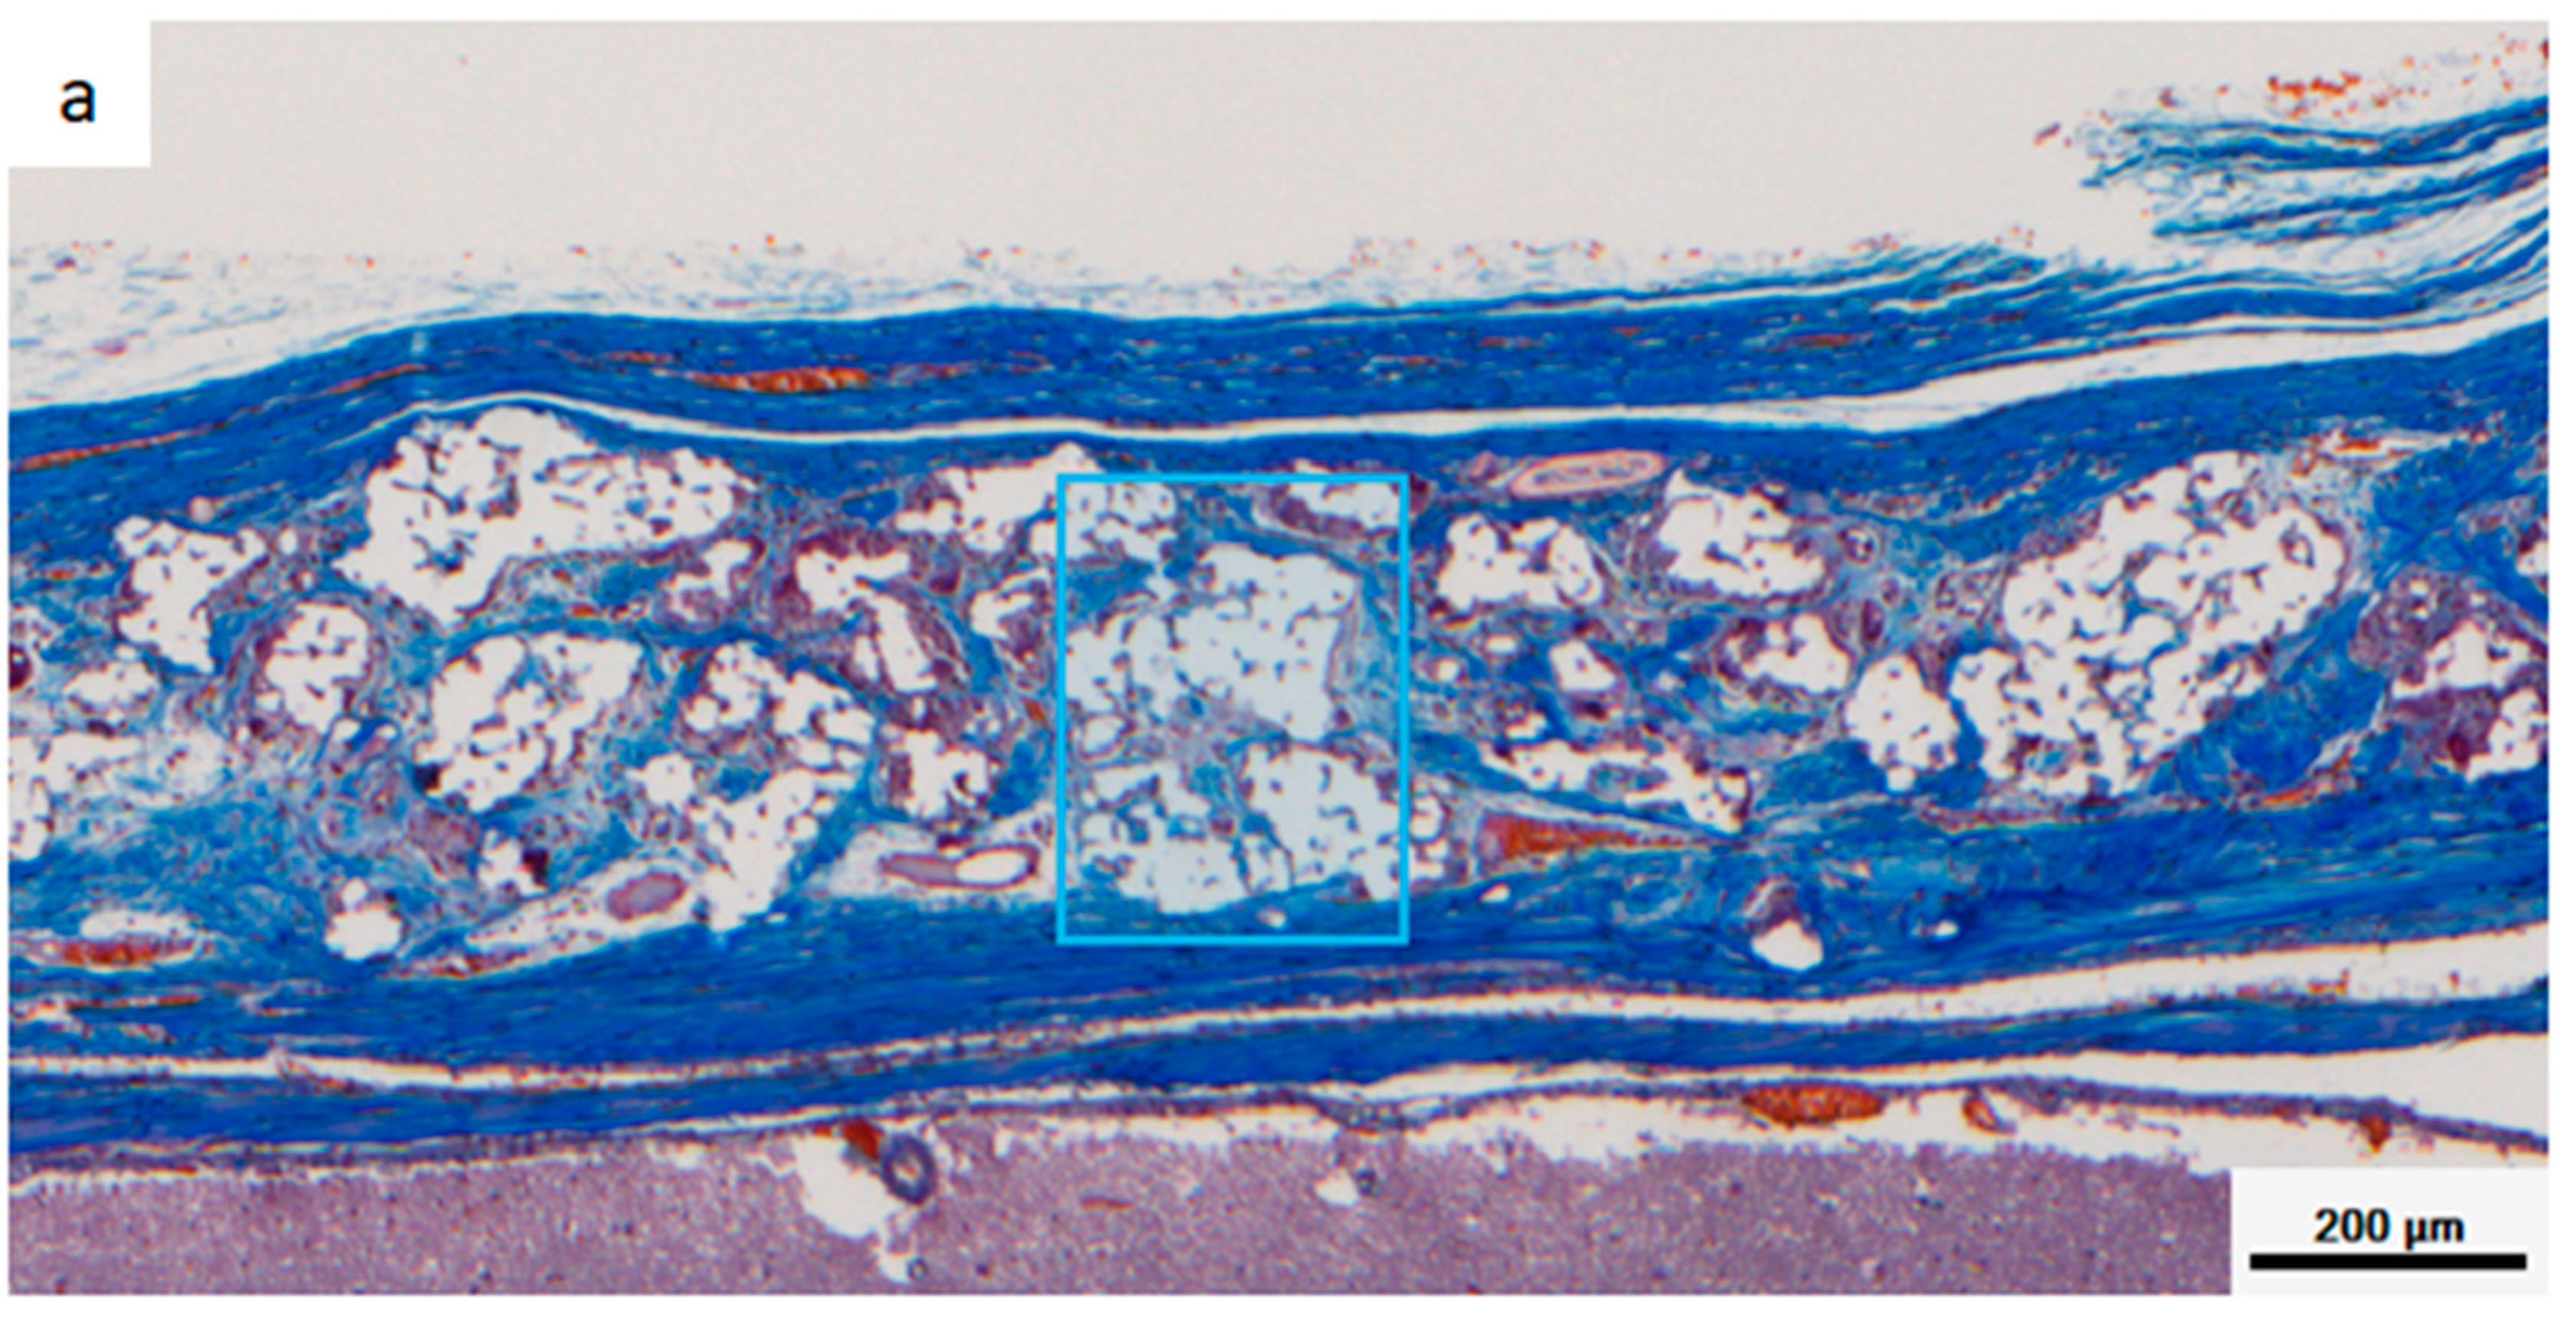

Figure 8 shows a multispectral image of MT-stained specimens in the CM and Sf-TCP groups. Aniline blue stains fibrous tissue blue, Masson liquid stains cells red, and Orange G stains blood cells orange. For quantitative analysis with inForm, CM and Sf-TCP existed in the bone defects.

Figure 8.

Masson’s trichrome (MT)-stained images taken with Vectra3. Aniline blue stains fibrous tissue blue, Masson liquid stains cells red, and Orange G stains blood cells orange. (a) CM implant at 4 weeks. (b) Sf-TCP implant at 4 weeks. The blue boxes indicate the area quantified in Figure 10.

Figure 9 shows an enlarged image of the region selected in Figure 8 and an image obtained by analyzing the corresponding portion with inForm. Cells and fibrous substances existed mainly in the periphery of CM in the CM group at 4 and 8 weeks, whereas in the Sf-TCP group, cells and fibers entered into the pores of Sf-TCP.

Figure 10 shows the results of quantifying areas of fibrous tissues and cells. Fiber and cell areas in the CM and Sf-TCP groups were compared at 4 and 8 weeks. The results showed that the fiber mass was significantly larger in the Sf-TCP group than in the CM group at both 4 and 8 weeks. However, actual cell amount did not change significantly.